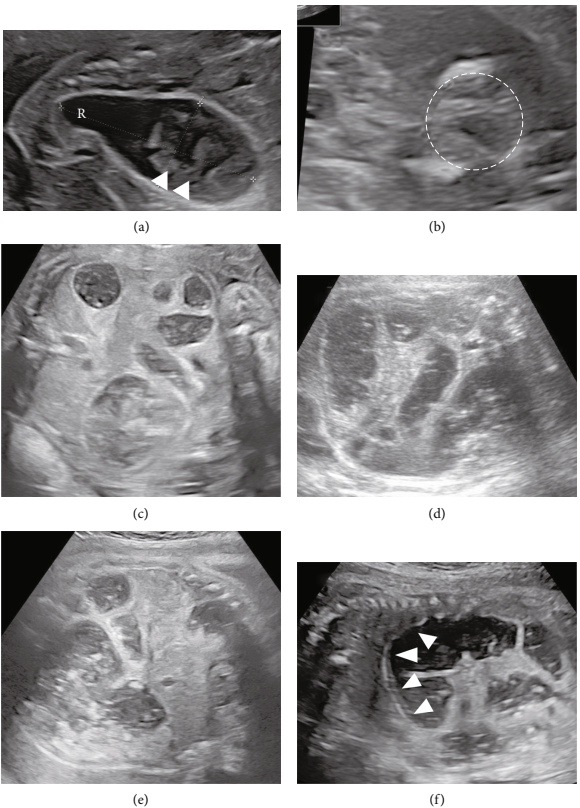

30岁孕妇,在怀孕19周时进行胎儿腹腔囊肿的产前评估。胎儿超声检查显示结肠扩张伴有肠钙化、直肠远端囊及肛门粘膜不可见,提示存在中/高位肛门闭锁伴直肠尿道瘘(图1 a-b)。未发现其他异常及胎儿生长受限。妊娠20周时的胎儿超声检查显示结肠扩张进展,羊水相对减少,但尚未出现羊水过少。即使告知父母胎儿可能预后不良,但父母仍不希望终止妊娠及羊膜穿刺术。从妊娠26周开始,胎儿超声检查显示肠道进一步扩张,导致胸部压迫,妊娠28周后羊水突然减少。尽管膀胱充满液体,但未见输尿管积水及肾积水,这意味着胎儿尿液流出阻塞的存在,而不是尿液产量的减少(图1 c-f)。

图1. 胎儿超声检查与胎儿肠道改变